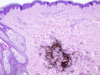

What disease process is pictured below?

Seborrheic keratosis

dark keratin-filled surface plugs (inset)

benign basaloid cells

prominent keratin-filled “horn” cysts, some of which communicate with the surface (pseudo-horn cysts).